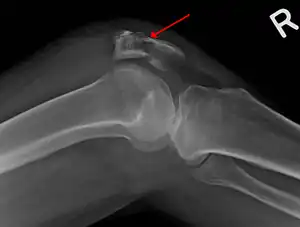

A fracture of the patella seen on a lateral view

Diagnosis is based on symptoms and examination, which typically reveals a swollen knee with reduced movement and a tender kneecap.[5] A fracture is subsequently confirmed with X-rays usually taken from different angles.[3] In children an MRI may be required.[3]